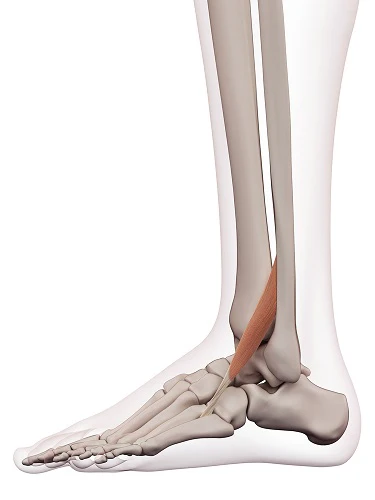

OIF of Plantaris and innervation

O: superior lateral condyle of femur

I: calcaneal tuberosity via Achilles Tendon

F: weak plantar flexion

Nerve: Tibial nerve